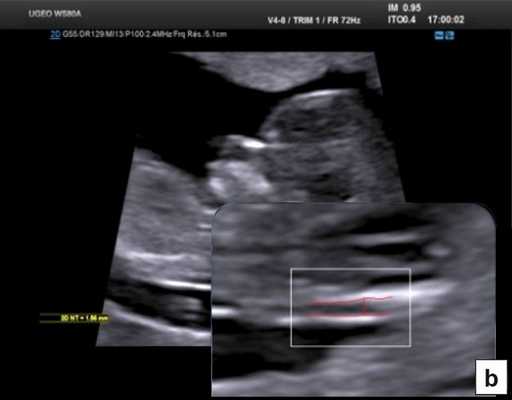

Описанные в литературе величины частоты выявления дефектов в I триместре беременности значительно различаются в зависимости от изученных популяций, методов и периодов [5]. По мере развития методов ультразвуковой диагностики усовершенствовался и анатомический анализ для I триместра беременности. Международное общество по применению УЗИ в акушерстве и гинекологии (International Society of Ultrasound in Obs tetrics and Gynecology - ISUOG) в 2013 г. предложило руководство для клинической практики, предполагающее проведение оценки анатомии плода между 11 нед 0 дней и 13 нед 6 дней беременности (рис. 3) [6].

Метод УЗИ позволяет выявлять в I триместре ряд аномалий развития плода:

- Видимые аномалии - анэнцефалия, алобарная голопрозэнцефалия, гастрошизис, омфалоцеле, аномалия предшественника аллантоидного стебелька, гидронефроз и некоторые несовместимые с жизнью остеохондродисплазии.

- Невидимые аномалии мозга, пищеварительной системы, урологические и скелетные аномалии.

- Некоторые аномалии, требующие анализа, - аномалии сердца, лица, конечностей, spina bifida.

Не так давно качество УЗИ в I триместре удалось повысить до уровня, позволяющего при рутинном ультразвуковом скрининге проводить полноценное диагностическое УЗИ. Достижения 3D/4D-методов и автоматизированные технологии измерения обеспечивают дополнительные возможности проведения точной анатомической оценки.

В 90% случаев крупные анеуплоидии у плодов можно обнаружить с помощью комбинированной оценки возраста матери, измерений ТВП и сывороточных маркеров у матери (РАРР-А и свободный бета-ХГЧ) [8]. Результат такого скрининга можно улучшить, исследуя сывороточные маркеры раньше, на сроках от 9 до 10 нед, и проводя УЗИ на 12-й неделе для выявления дополнительных маркеров, таких как носовая кость плода, кровоток в венозном протоке и через трехстворчатый клапан (рис. 5) [9]. Кроме того, выявлять часто встречающиеся хромосомные аномалии у плода позволяет неинвазивное пренатальное тестирование (Non Invasive Prenatal Testing - NIPT).

Рис. 5. Оценка анеуплоидии по ультразвуковым маркерам: толщина воротникового пространства (a), носовая кость (b), венозный проток (c), кровоток через трехстворчатый клапан (d).

Тем не менее "базовое" УЗИ обычно дополняют исследованием в цветовом энергетическом допплеровском режиме с тщательным анализом для выявления атриовентрикулярного кровотока в четырех камерах сердца (рис. 6a) и в срезе через три сосуда и трахею (рис. 6b). Получив эти срезы, обычно можно успокоить родителей, исключив наличие тяжелых пороков сердца, таких как единственный желудочек, гипоплазия желудочков, полный дефект предсердно-желудочковой перегородки (atrioventricular septal defect - AVSD), атрезия аорты или легочной артерии, а также ряд аномалий расположения артерий.

Рис. 6. Эхокардиография плода на ранних сроках в цветовом энергетическом допплеровском режиме - визуализируются четыре камеры (a) и срез через три сосуда и трахею (b).